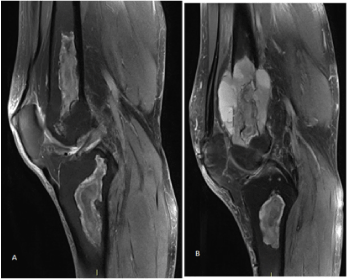

Figure 2. Pathological fracture of left distal femur and postoperative X-ray film of megaprosthesis reconstruction